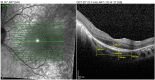

Figures